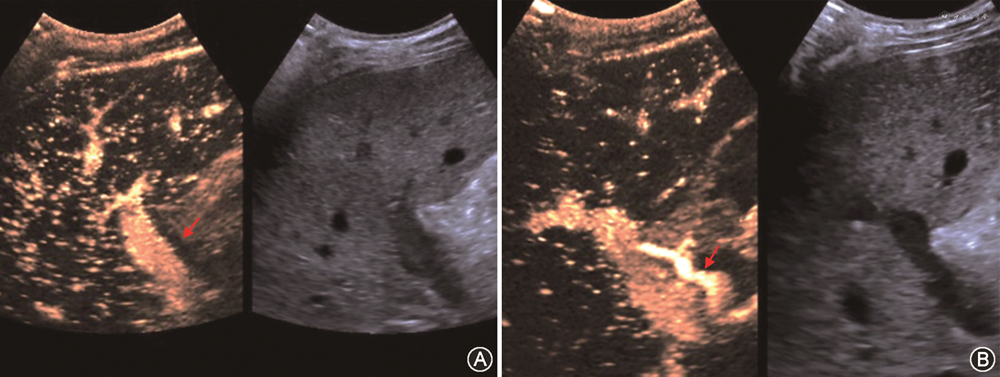

(2)肝静脉或下腔静脉血栓:肝静脉或下腔静脉血栓与外科吻合技术及患者处于高凝状态均有关。声像图表现为肝静脉或下腔静脉附壁见实质回声,CDFI示局部血流充盈缺损。增强CT或增强MRI可观察到静脉相应引流肝段的血流灌注改变。肝中静脉属支血栓闭塞时,静脉相应引流肝段血流灌注改变,超声造影检查可见受影响区域肝实质动脉期呈片状高增强,门静脉期消退为片状低回声。超声造影诊断肝中静脉属支血栓闭塞,假阳性率从CDFI诊断时的14%下降为3%[81]。需注意,术式如果为“背驮式”肝移植,其静脉吻合的盲端处常可见血栓形成,该血栓通常无不良临床后果。

(2)胆道狭窄:胆道狭窄包括吻合口狭窄和非吻合口狭窄。吻合口狭窄较常见,多表现为手术吻合口附近5 mm内的孤立狭窄,与吻合技术不当有关,其中位发生时间是移植术后5~8个月。非吻合口狭窄指距离手术吻合口>5 mm的不规则狭窄,可在肝门部或肝内胆管多处发生,多与胆管缺血有关,故又被称为缺血性胆道病变[82,86],发生时间多在移植术后3~6个月。吻合口狭窄声像图主要表现为胆管吻合口处狭窄伴肝内胆管规则连续扩张;超声还可显示因狭窄导致胆汁引流缓慢而出现的胆泥或结石;经胆道超声造影对显示肝外胆道狭窄的部位及程度有一定价值[3]。缺血性胆道病变时,CDFI检查示肝内胆管为跳跃性、节段性不规则扩张,可合并胆管铸型、胆汁瘤及胆漏(图19);超声造影检查可观察到肝门部胆管壁动脉期无增强或低增强,以该特征诊断缺血性胆道病变的灵敏度、特异度及准确性分别为66.7%、88.9%及76.2%[86, 87]。需注意,超声检查发现移植肝胆道狭窄时,应同时检查肝动脉通畅情况,排除肝动脉并发症可能[88, 89]。MRCP能清楚显示包括胆道狭窄段的胆管全程,诊断胆道狭窄阴性预测值高。因此,评估移植肝胆道狭窄,超声与MRCP联合应用更有诊断价值[90, 91]。